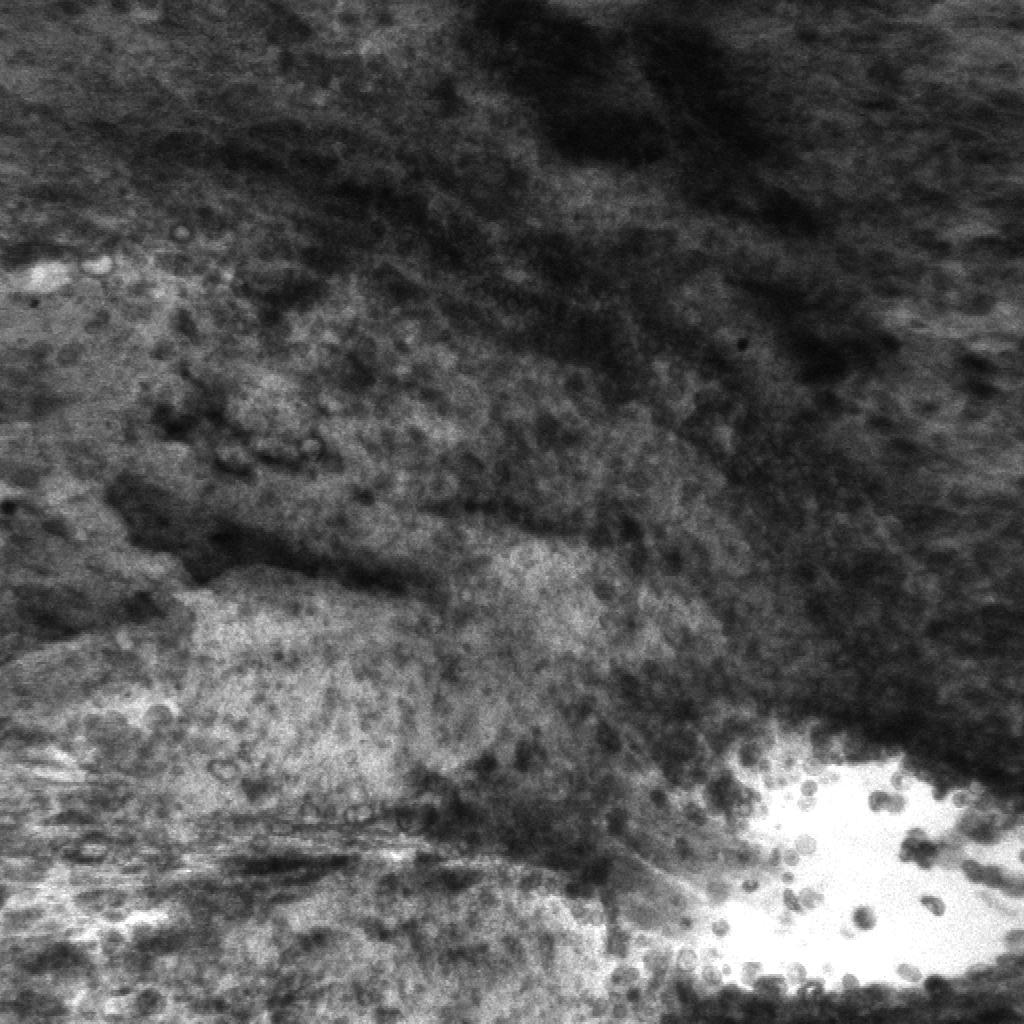

Figure 5: Unsupervised localization of the histopathological features from shallow and deep neurons inside the network. First column (a, e, i) shows the input CLE images from human glioblastoma obtained intraoperatively. Second column (b, f, j) displays activation of neurons from the first layer (conv1, neuron 24) (shallow features); it highlights some of the cellular areas present in the image. Third column (c, g, k) illustrates diagnostic regions of interest identified with sliding window approach. The boxed regions represent high activation of the deepest network neuron. Fourth column (d, h, l) contains images extracted from conv1 activation (neuron 22), representative of the high fluorescence signal, a diagnostic sign of blood-brain barrier disruption and leakage of fluorescent agent from the vessels into the extracellular space.

5.3 Histological features localization

8 out of total 384 reviewed colored neuron activation maps from the first layer were selected for 4 diagnostic CLE images representative for glioma. Selected activation maps highlighted diagnostic tissue architecture patterns in warm colors. Particularly, several maps emphasized regions of optimal image contrast, where hypercellular and abnormal nuclear features could be identified, and would serve as diagnostic features for image classification (Fig. 4.1, columns 2 and 4). Additionally, sliding window method was able to identify diagnostic aggregates of abnormally large malignant glioma cells and atypically hypercellular areas (Fig. 4.1, third column).

Activation of the neurons in the first convolutional layer (conv1) were found to highlight areas with increased fluorescein signal, a sign specific to brain tumor regions. Increased fluorescent signal on CLE images represent areas with blood brain barrier disruption which correspond to the tumor areas visible on a contrast enhanced MR imaging. Interestingly, sliding window method and selected colored activation maps were not distracted or deceived by the red blood cells contamination, as they mostly highlighted tumor and brain cells rather then hypercellular areas due to bleeding. The proposed feature localization approach may be useful in the future to aid in the identification of not only the diagnostic frames, but also directing the surgeon’s attention to the image parts containing major histopathological features.